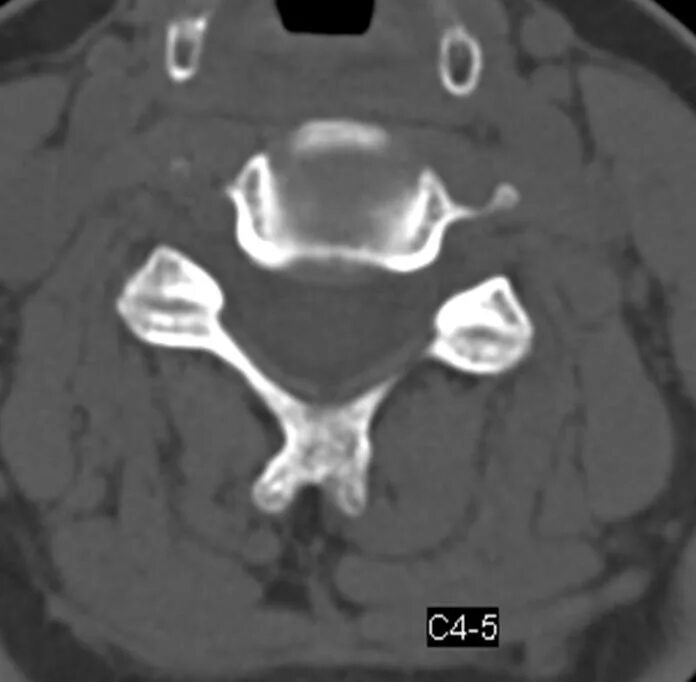

Спондилоартроз кт